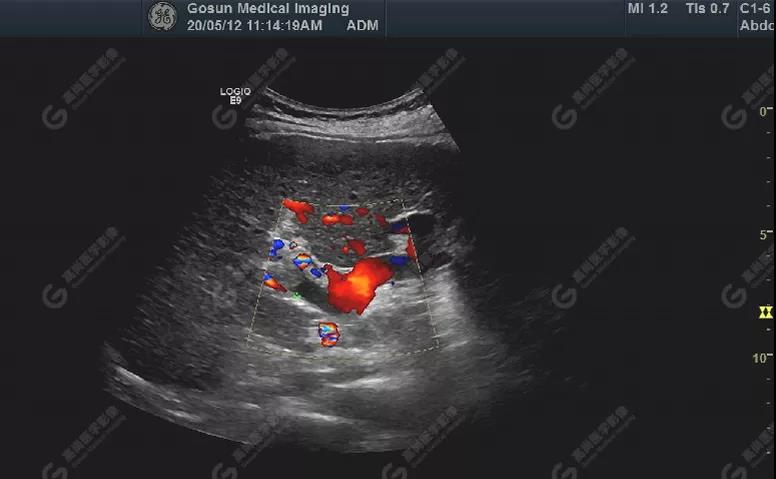

門靜脈右支內(nèi)低回聲處可見血流充盈缺損,其內(nèi)部無明顯血流